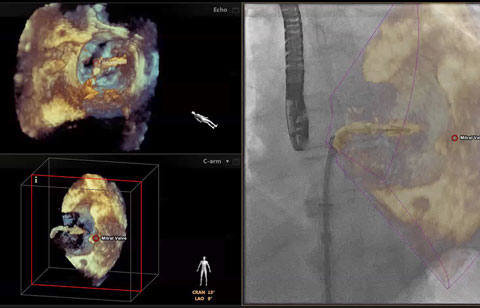

يمكّن الربط بين تقنية Live 3D TEE والأشعة السينية المستخدم من فهم الحيز ثلاثي الأبعاد بسهولة ومن دون الحاجة إلى محاذاة العرضين معًا ذهنيًا.

زيادة رؤية الهياكل القلبية باستخدام تخطيط الصدى المرتبط بالتنظير. ويتم تحديث التوجيه بصور تخطيط الصدى تلقائيًا عند تغيير وضعية ذراع أنبوبة الأشعة على شكل C. وتظهر العلامات الموجودة على الهياكل التشريحية للأنسجة الرخوة في تخطيط الصدى تلقائيًا في صورة الأشعة السينية لتوضيح سياق العمل والتوجيه. ويستطيع جميع أفراد الفريق الطبي تقدير موضع جهاز إصلاح الصمام الميترالي باستخدام القسطرة وحالة عرضه في الوقت الفعلي وبدرجة وضوح شديدة.